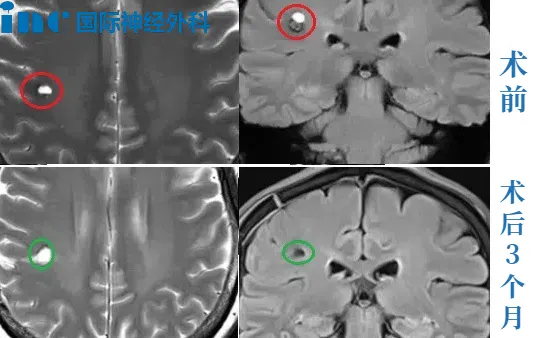

23岁男性•半卵圆中心海绵状血管瘤术后两周出院

简要病史:右手无力,写不了字,23岁的斌斌就医检查左半卵圆中心海绵状血管瘤,住院治疗一周,期间右腿、右脚无力,走路不利索,医院给予保守治疗后出院。斌斌父母一直苦苦寻求能为年轻的孩子安全手术的主刀医生。当他们看到了巴教授来华示范手术消息,于是奔赴苏州寻求教授为孩子主刀手术。

治疗过程:在苏州大学附属第四医院,巴教授已经顺利为斌斌顺利完成手术,全切左半卵圆中心海绵状血管瘤。

术后情况:术后一周,已经可以自行下床活动,术后的右手麻木等症状有所缓解,术后两周多顺利出院,现在早已恢复正常生活重回大学校园。